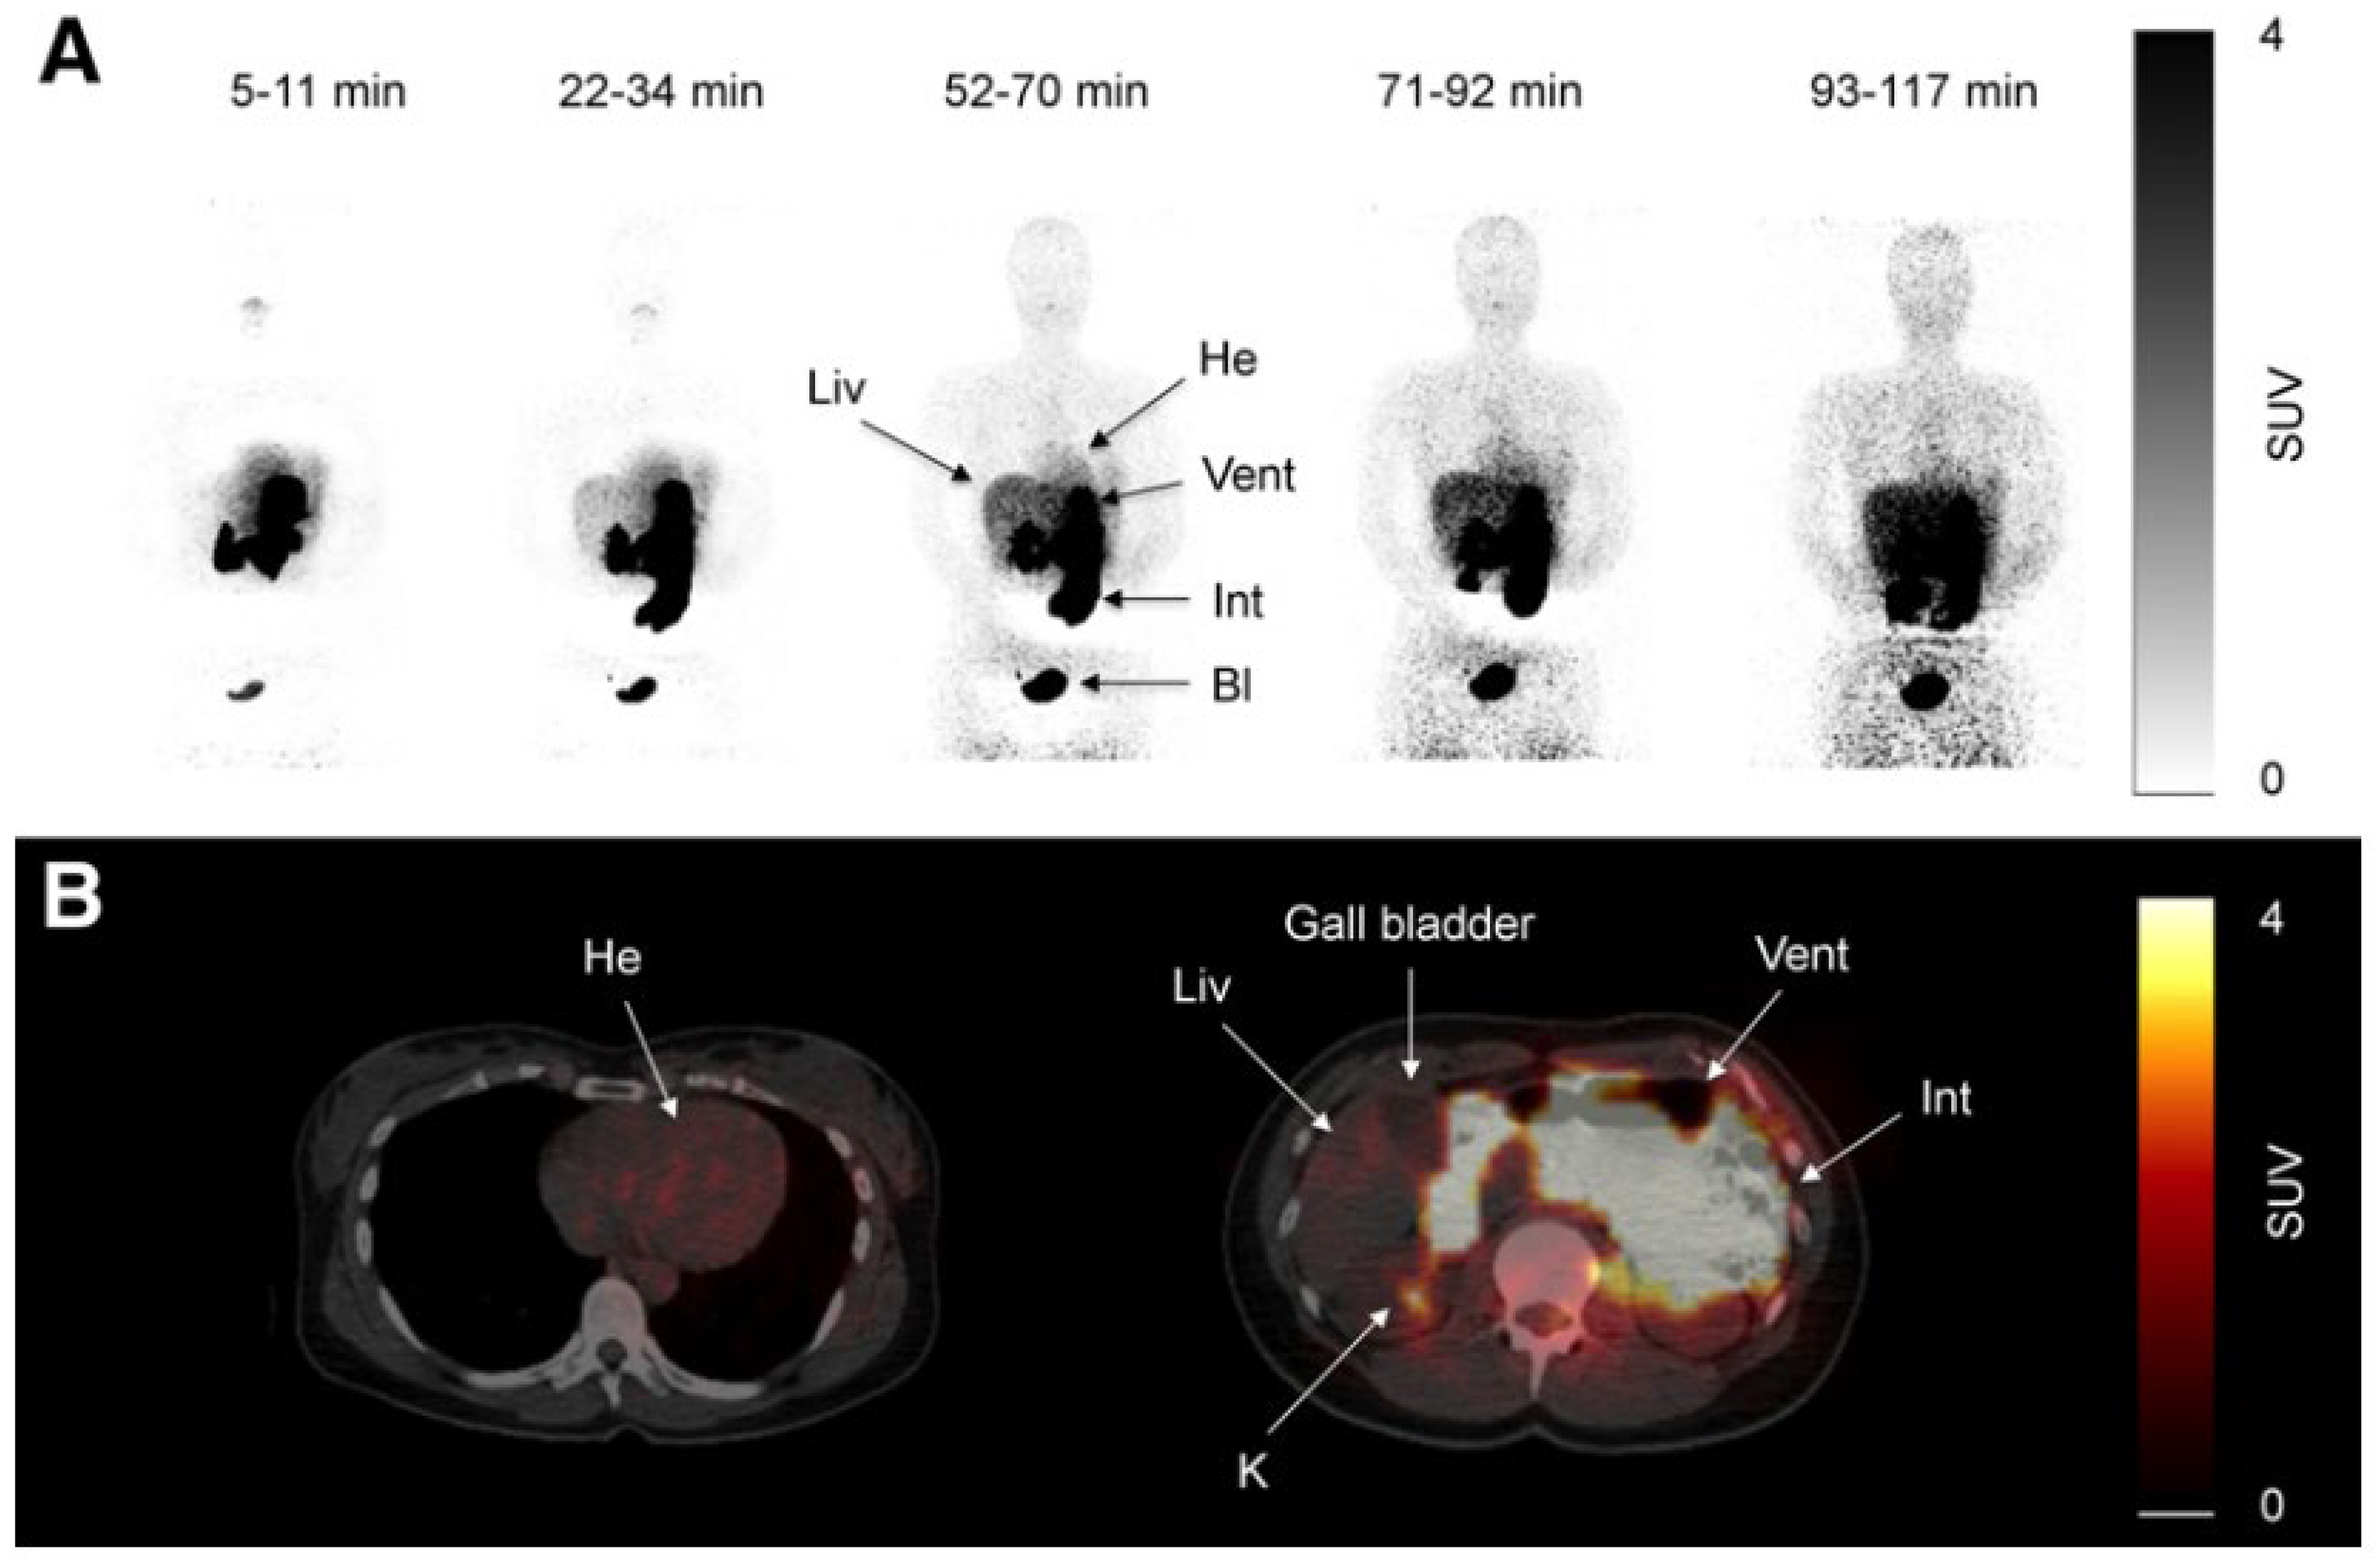

C11-metformin (9.5 microSv/MBq = ca.1.1 micrograms), first injected intravenously, allowed the study of its biodistribution in humans by the PET scan technique [133]. Most of the activity was found in the liver, the kidneys, and the urinary bladder. Most of the absorbed compound was cleared from the blood 20 min after injection. Dosimetry calculations were performed for the stomach-, small intestine-, liver-, kidney-, and bladder contents. It was demonstrated that hepatic metformin uptake is very rapid and fully reversible, but the accumulation of the activity was higher than after intravenous administration since, although slower, the tracer delivery came from the portal blood through the liver first. Two hours after the oral ingestion of the tracer, the bulk of the radioactivity was still found in the intestine (Figure 1 lower panel), and no further observation of the fate of the radioactive metformin was possible.

Although an active transport of metformin through the membrane of the hepatocyte was extensively discussed by Gromensen et al. [133], it has to be mentioned that hepatic densitometry pictures similar to those observed after intravenous and oral administration of C11-metformin can also be observed after the injection of C11-nicotine [136] or even of C11-donepezil, a high-affinity antagonist of acetylcholinesterase normally used as drug in the treatment of patients with Parkinson’s disease [137,138]. It cannot be ruled out that there is a diffusion into the space of Disse through the fenestrae of the sinusoidal endothelial cells [132] and that the compound is then washed out from the interstitium back into the hepatic vein. It may be therefore more appropriate to speak about hepatic metformin “extraction” [139] than about uptake.

The kidney-to-blood activity ratio was identical independently of the administration route of the radioactive metformin. Some discrete uptakes of the tracer was found in the salivary glands, and discrete uptake was found also in the intestine. No activity was found in the gallbladder. Significant amounts of the tracer passed to the small intestine 10 min after ingestion.